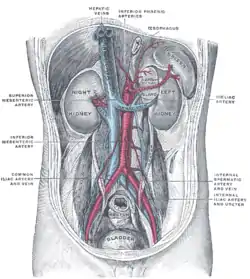

Animated Volume rendered CT scan of abdominal and pelvic blood vessels. Posterior abdominal wall, after removal of the peritoneum, showing kidneys, suprarenal capsules, and great vessels. (Hepatic veins labeled at center top.)

Posterior abdominal wall, after removal of the peritoneum, showing kidneys, suprarenal capsules, and great vessels. (Hepatic veins labeled at center top.) Human embryo with heart and anterior body-wall removed to show the sinus venosus and its tributaries.